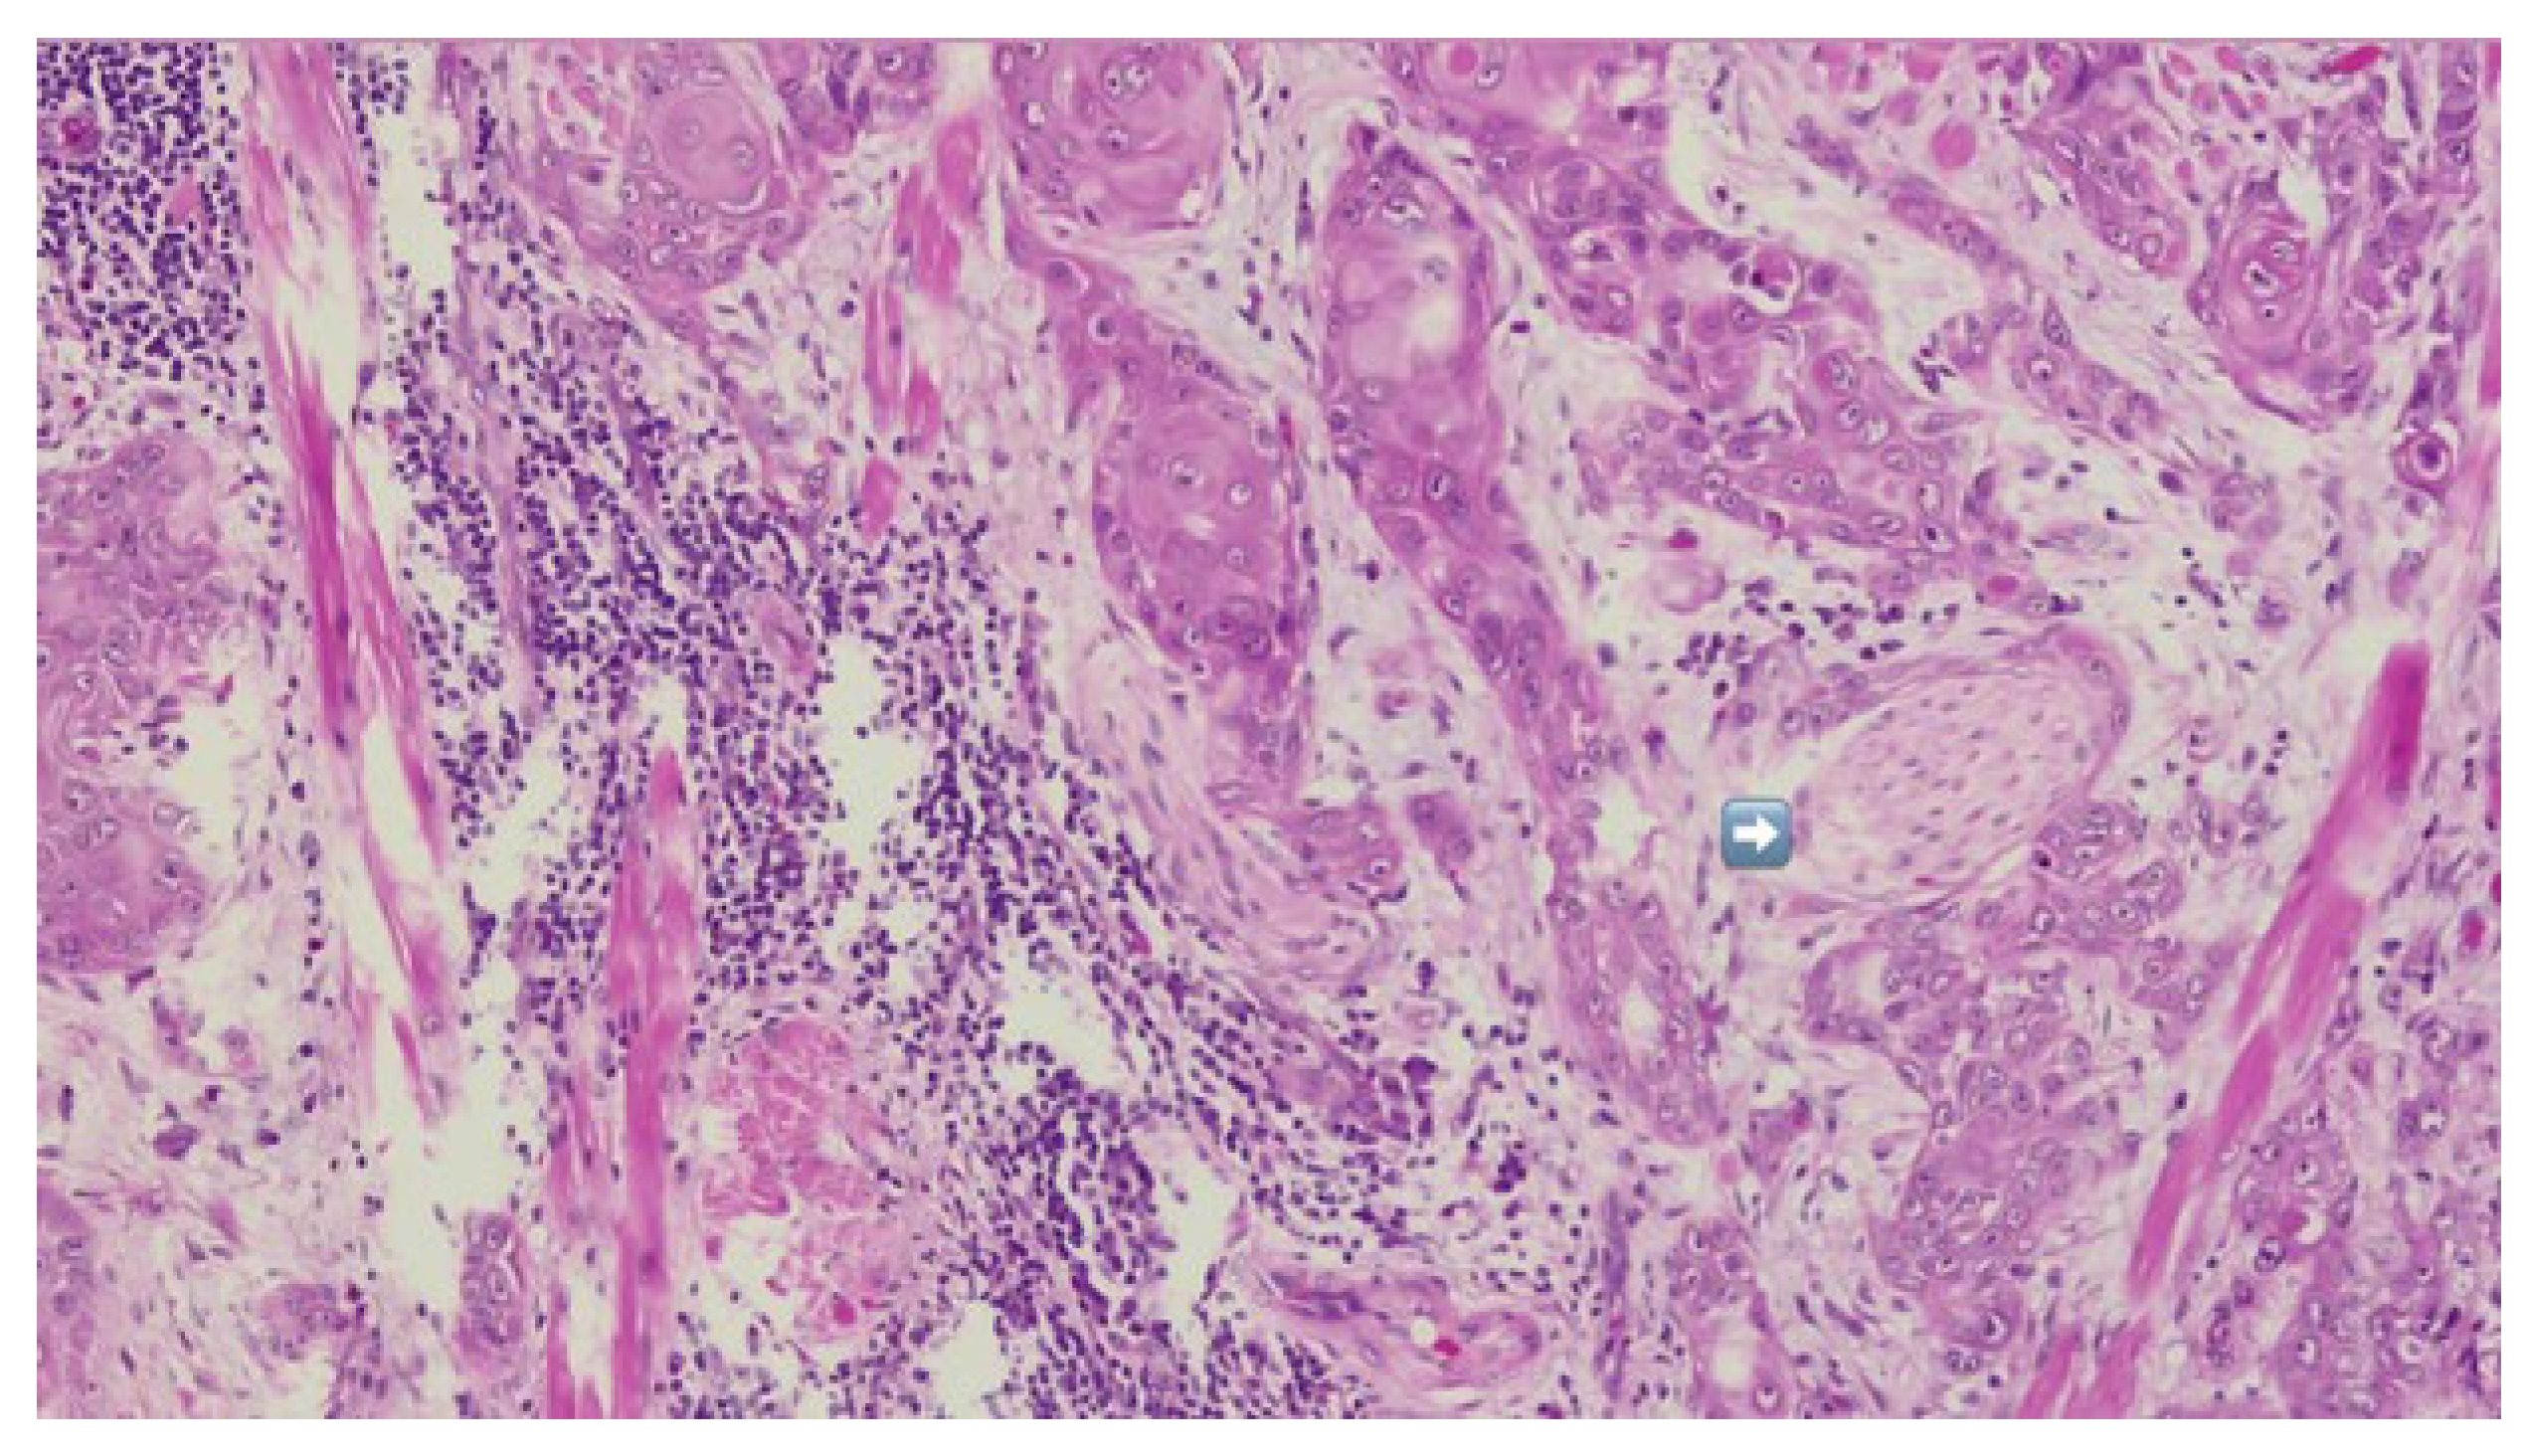

Tumor resection was subsequently performed with a macroscopic oncologic safety margin of approximately 1 cm. The primary surgical specimen, including the neoplasm, associated lymph node groups, and the submandibular salivary gland, was removed en bloc via a transoral approach. The specimen was immediately fixed in 10% buffered formalin and submitted for definitive histopathological evaluation (Figure 7).

Figure 7.

HE-infiltrative squamous cell carcinoma with peri-neural invasion—indicated by blue arrow.

Definitive histopathological analysis of the surgical specimen confirmed a moderately differentiated keratinizing squamous cell carcinoma with evidence of perineural invasion (Figure 7). All surgical margins were free of tumor infiltration (R0 resection). Examination of the lymph nodes removed during selective neck dissection revealed no metastatic involvement (0 nodes). No evidence of distant metastasis was identified on preoperative imaging or postoperative staging, confirming a final pathological stage of pT3N0M0 (Stage III) according to the AJCC 8th edition.